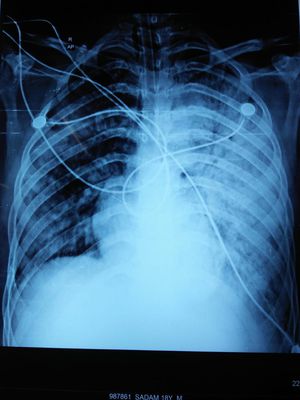

Xray of post op neurosurgery patient spo2 decreasing .pt is having brain edema and is on vent .

VAP or pulmonary edema maybe. increase dosage of diuretic. Aspiration intratracheal secretion and sending smear and culture recommended.